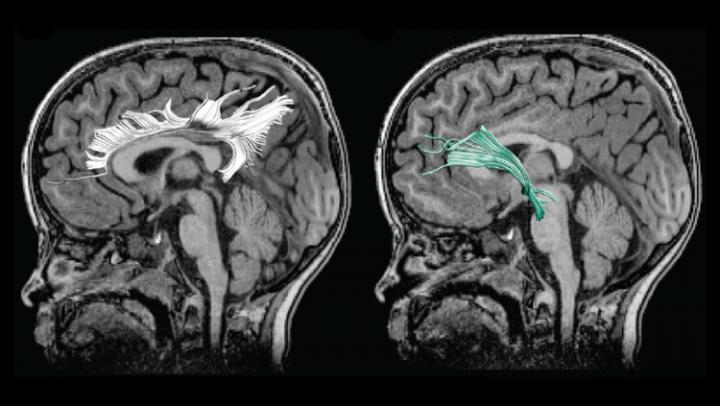

Hay et al. studied 54 mother/child pairs. Mothers answered a survey about their depression symptoms at several points during their pregnancy. The research team employed diffusion MRI, an imaging technique that reveals the strength of structural connections between brain regions, to examine the children's white matter.

Greater prenatal depression symptoms were associated with weaker white matter connections between brain regions involved in emotional processing. This change could lead to dysregulated emotional states in the children and may explain why the children of depressed mothers have a higher risk of developing depression themselves. The weakened white matter was associated with increased aggression and hyperactivity in the male children. These findings highlight the need for better prenatal care to recognize and treat prenatal depression in order to support the mother and the child's development.

Manuscript title: Amygdala-Prefrontal Structural Connectivity Mediates the Relationship Between Prenatal Depression and Behaviour in Preschool Boys